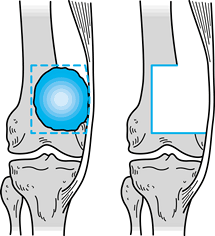

perform an arthroplasty of the knee after resection: (a) osteoarticular

arthrochplasty, and (c) modular prosthetic arthroplasty. Each has

use biological tissue to restore either bone stock or bone stock with

an articular surface. The osteoarticular allograft replaces the missing

bone and, in addition, serves as

a joint surface (22,43,82,83,84 and 85,91,121,147) (Fig. 126.13). Typically, these are frozen grafts from an accredited tissue bank (132). It is critical to screen all biological tissue for both viral and bacterial contamination (43,133).

Figure 126.12. Reconstructive techniques. A: Osteoarticular allograft. B: Allograft prosthetic composite.